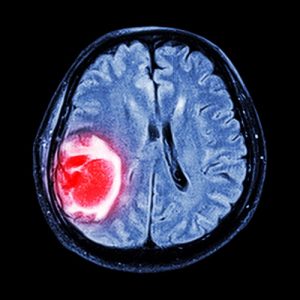

Опухоли мозга – болезни, которые беспокоят не только взрослых, но и детей. В настоящее время идентифицированы различные виды внутримозговых опухолей как доброкачественного, так и злокачественного характера, которые могут встречаться у пациентов до 18 лет. Вот список некоторых наиболее распространенных опухолей, с которыми часто сталкиваются израильские нейроонкологи и детские нейрохирурги:

Точные причины развития внутримозговых опухолей у детей и взрослых до сих пор неизвестно. Предполагается, что существенными факторами появления опухолей в тканях мозга могут служить черепно-мозговые травмы, наследственная предрасположенность, вирусные инфекции, а также действие токсических и канцерогенных веществ. Коварство таких патологий в том, что симптомы на начальных стадиях развития часто отсутствуют. Более того, часто пациенты десятками лет не догадываются о своих опухолях в мозге, и обнаруживаются они случайно при обследовании. Отметим, что некоторые доброкачественные опухоли мозга никак не отражаются на состоянии здоровья пациента. В таких случаях врачи рекомендуют пациентам регулярно обследоваться, чтобы держать опухоль под контролем. Признаки увеличения размеров опухоли, а также ухудшение состояния больного в связи с опухолью являются основанием для скорейшего медицинского вмешательства.

- МРТ, КТ, ПЭТ.